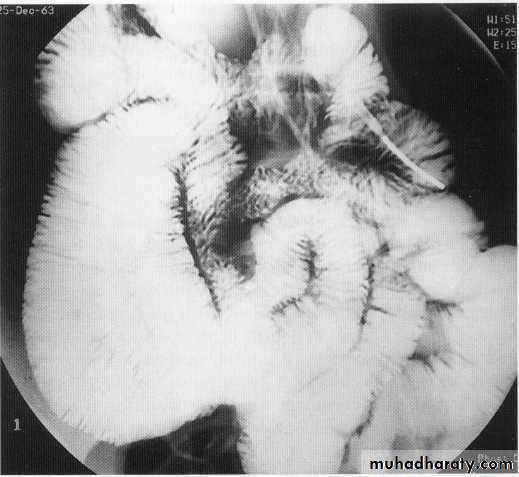

Chrons disease

Chrons stricture